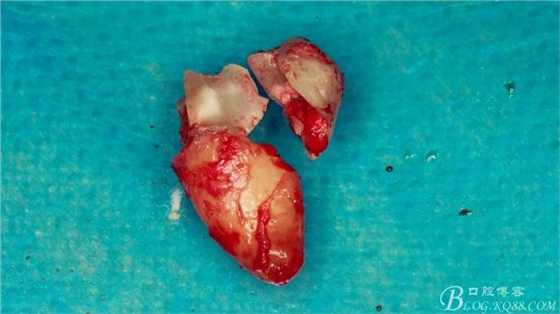

牙齒分為了三部分。

術(shù)后常規(guī)遺囑,患者回訪表示連止疼藥都沒吃,幾乎沒有太大的不適感。